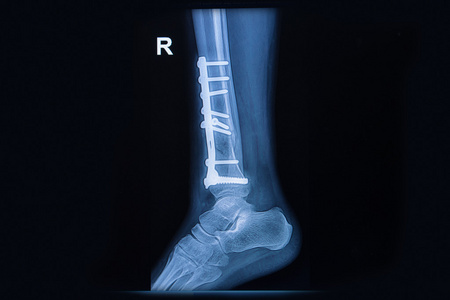

闭合复位交锁髓内钉治疗粉碎性胫腓骨骨折 复旦大学附属上海市第五人民医院

2个典型病例教会你踝部骨折外固定 医学界 助力医生临床决策和职业成长

医疗 我院成功行右侧三踝粉碎性骨折切开复位内固定术